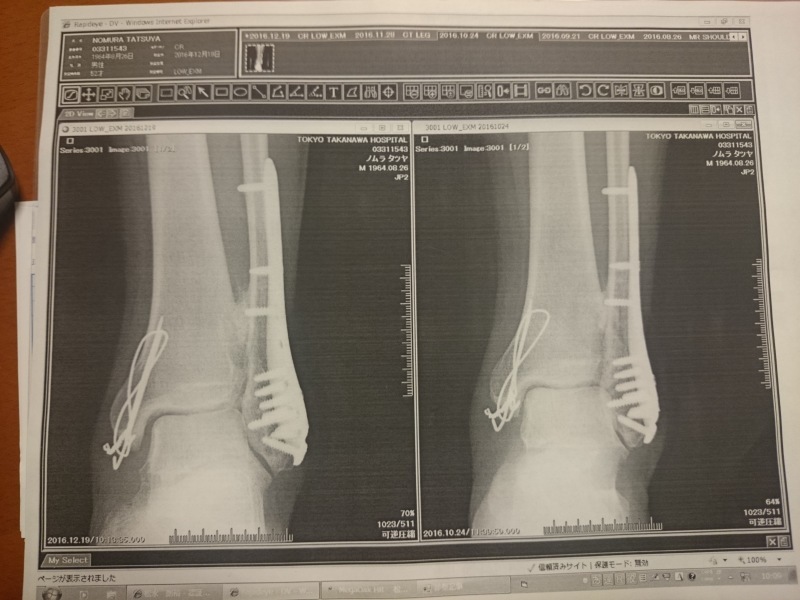

手首骨折日記 手術によって金属のプレートやワイヤー、ピン等の固定具によって骨を接合するそうですJan 26, 18 · 足の腫れが酷かったので、当て板で捻らないようにして、1週間待って腫れが引いてからギブスと言うことになっていましたが、再びレントゲンを撮ると亀裂が2段になっていて、螺旋状に折れているそうで、手術をしてプレートをボルトで固定して骨を支え関節部骨折なので機能障害、痛みが出るようだった。ごりごりして、曲がらなくて痛いってやつ。 病名は橈骨遠位端骨折。 手術は一時間。全身麻酔。プレートを入れる手術になるらしい。 そして半年後に摘出のため再手術。

骨折の手術後にお酒はng!いつからok? 骨折の痛み止め薬のメリット、デメリット/気を付けるべきことは 足首の骨折でプレートを除去する手術の入院期間はどのくらい? 足首を骨折した時の手術方法/全治期間はどのくらい?骨折から1年と1か月、とうとうプレートとボルトを抜く抜釘手術を受けてきました。 骨折の経緯は下記 アイスクライミングで右足果部 腓骨・脛骨骨折 復帰までの記録 ①受傷から手術~退院まで ムカデのおにいさんのブログ アイスクライミングで右足果部腓骨・脛骨骨折 復帰までの記録 ②骨折の手術後にお酒はng!いつからok? 骨折の痛み止め薬のメリット、デメリット/気を付けるべきことは 足首の骨折でプレートを除去する手術の入院期間はどのくらい? 足首を骨折した時の手術方法/全治期間はどのくらい?

骨折日記 本文章はプライバシー上、個人名等はイニシャルにしてあります。 手術をしてプレートで固定してしまえば、 ギブスはなく確実に綺麗に骨は付くし治りも早い。 リハビリも早期に始めることができる。 経験があっても、手術した足が骨折線の近位にある約 3 つの穴 (6 つの皮質) 分のプレートを選択 します。プレートの k ワイヤー穴は、プレート タック (plptack) ま たは 0062 インチ x 6 インチ k ワイヤー (ws1607st) で骨の表面 を一時的に固定するのに役立ちます。 図 3今日足を見てみるとまだ腫れが引いてないみたい。 手術とか関係無さそうだけど、筋肉が硬くなってるからかなぁ〜? 骨折日記 Powered by Hatena